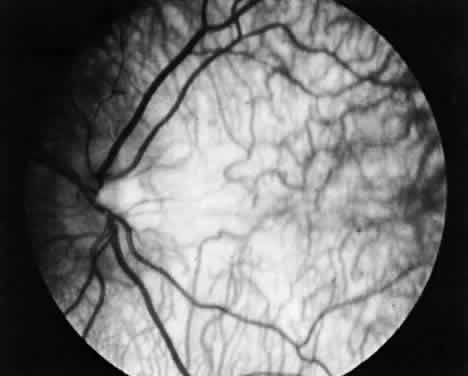

During late childhood, sharply demarcated, circular areas of chorioretinal degeneration in the midperiphery can be detected. There may be increased pigmentation around the margins of these lesions. During the second decade, the lesions enlarge, coalesce, and extend toward the posterior pole of the retina (Fig. 8). By the third decade, much of the retina is involved, although foveal lesions are rarely present until very late in the course of the disease. Histologic examination of an affected retina has shown focal areas of photoreceptor atrophy with adjacent retinal pigment epithelial hyperplasia. Electron microscopy has revealed mitochondrial abnormalities of the photoreceptors.114

Fig. 8. Fundus in gryrate atrophy. (Courtesy Richard Lewis, MD)